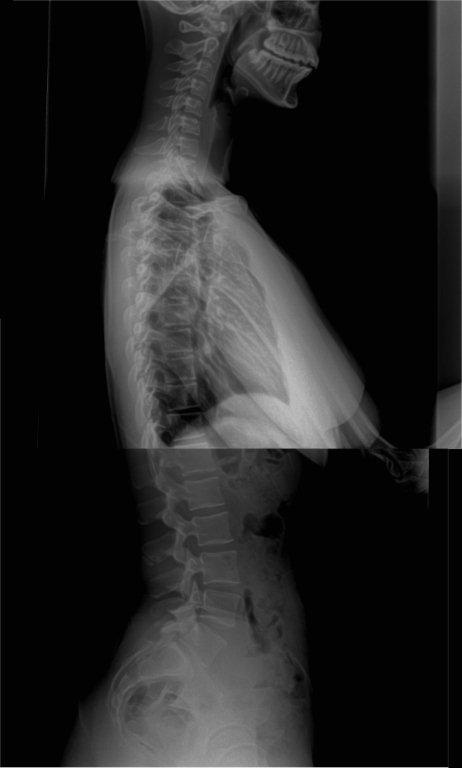

Along with my malalignment story, I would like to share some details pertaining to my daughter, Ally, at age 18 regarding her SI dysfunction and its related malalignment syndrome . Click on X-rays to enlarge.

Here are the diagnostic findings on her full spine x-rays provided by Dwyer Chiropractic Center:

- Sacral apex angle of 24 degrees (normal is 45 degrees)

- 6 degree angle on L5 (normal is 10-15)

- 1mm of anterior rotation and 7 mm of internal rotation on her left ilium

- 4mm of posterior rotation on her left side of sacrum

- Mild left lateral curve in her lumbar region, even leg length upon analysis (also confirmed by prior limb length study), reverse cervical curve

IMPRESSION:

- Left pelvic subluxation

- Posterior and Inferior L5 subluxation

- Posterior sacral apex with left posterior rotation

- Healed L3 spinous tip fracture

- Reverse cervical curve with anterior head carriage